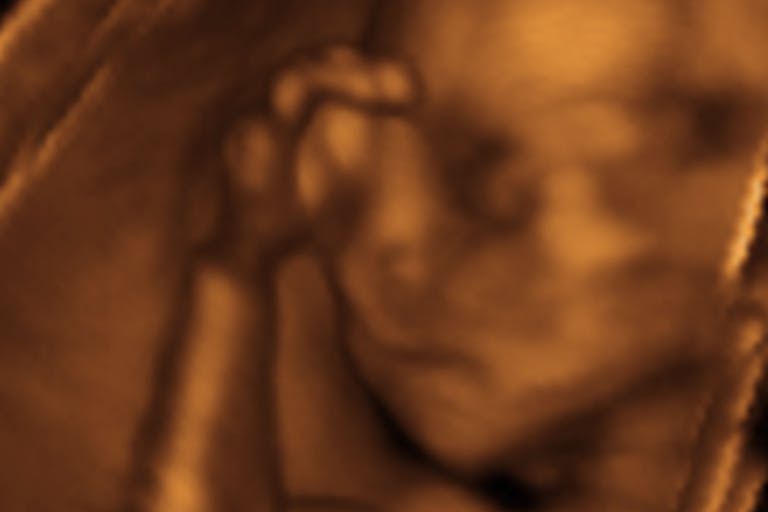

We know it, the abortion industry knows it. When women get the facts about human life and see an ultrasound of their unborn child, they are less likely to abort their child. One of our recent undercover videos shows abortion clinic staff basically admitting this to us:

In Florida, the legislature has passed a law that requires an ultrasound to be done before an abortion and women given the option to view the ultrasound. Women would also be given a medically accurate description of the unborn child’s current development.